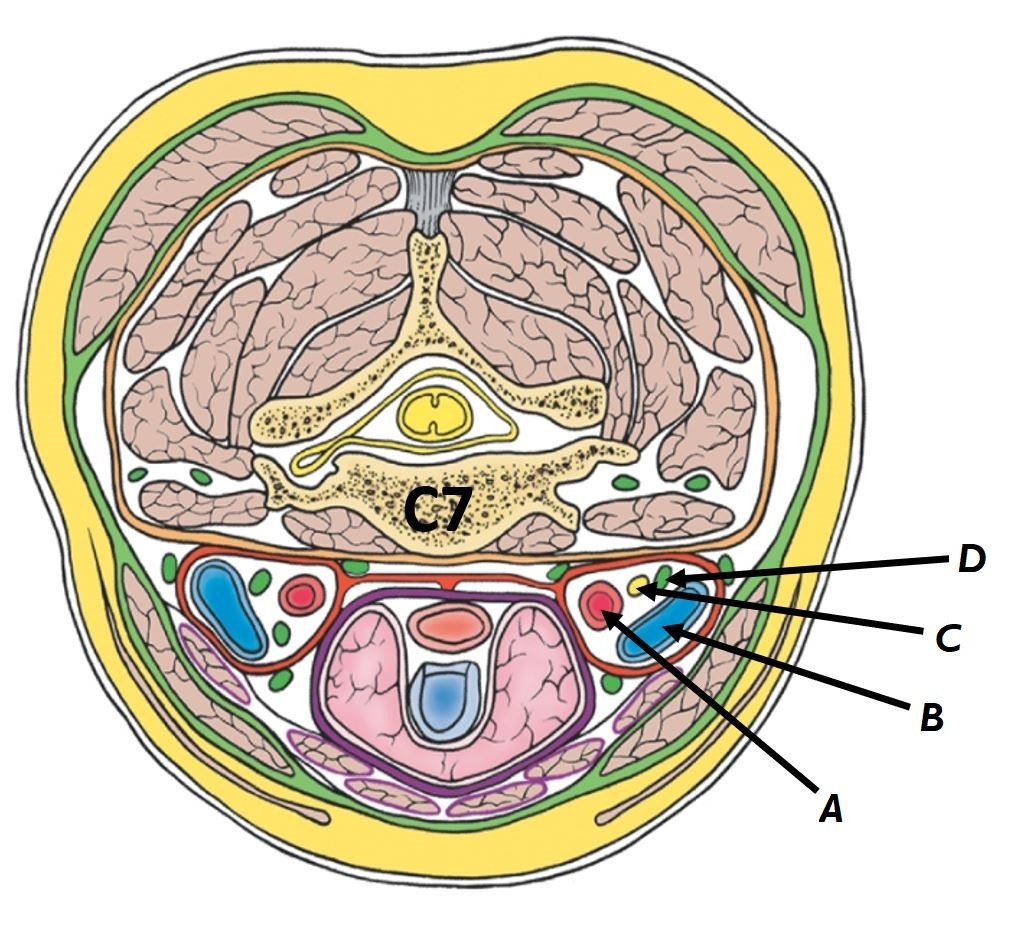

Name structures A to D

A - Common carotid artery

B - Internal jugular vein

C - Vagus nerve

D - Deep cervical lymph nodes